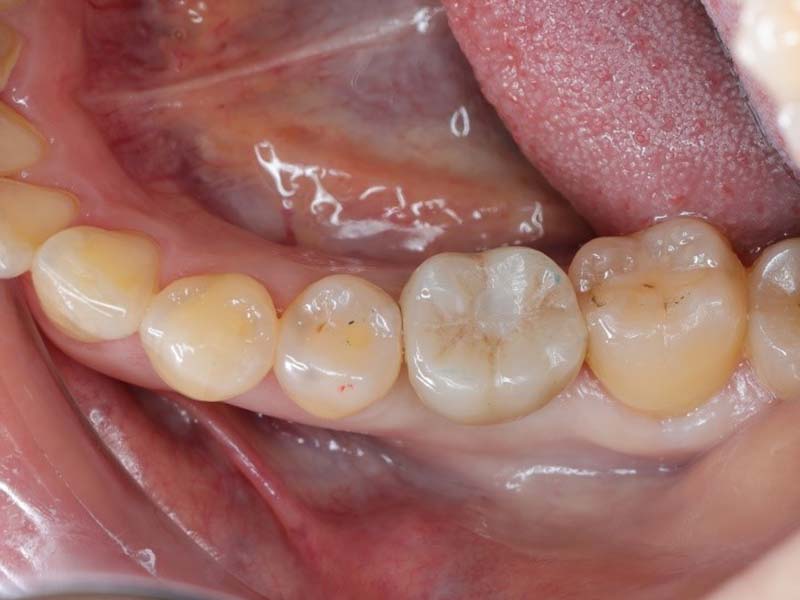

術前透過電腦模擬植牙位置,考量骨密度及咬合位置。制定最佳治療方案,使用數位化設備輔助,避開神經位置,降低植牙手術造成神經損傷的風險。也可以讓未來假牙贗復的結果為理想咬合的位置。

因為預先進行模擬設計,符合個人口腔型態及條件,大幅縮短整個治療時間。

植牙的成功與否不只要靠醫師的技術,還要加上術前仔細評估、手術過程精準、術後照護等因素,才能保證植牙治療的品質。 根據醫學研究報告顯示,一旦植體放入的位置不當,不僅會造成往後的假牙製作不易,更容易出現斷裂或發炎等問題,導致植牙失敗。在植牙過程中,病患不自主的小動作(如吞嚥口水、嘔吐反射、嘴巴張不開等),也都會影響植體放入的角度,只要位置不夠精準,植牙治療效果就會大打折扣。植牙手術導板可製化,針對不同病患設計,提高植牙成功率。建議民眾在接受植牙治療時,可藉由植牙手術導板精準定位,達到成功植牙的治療成果。